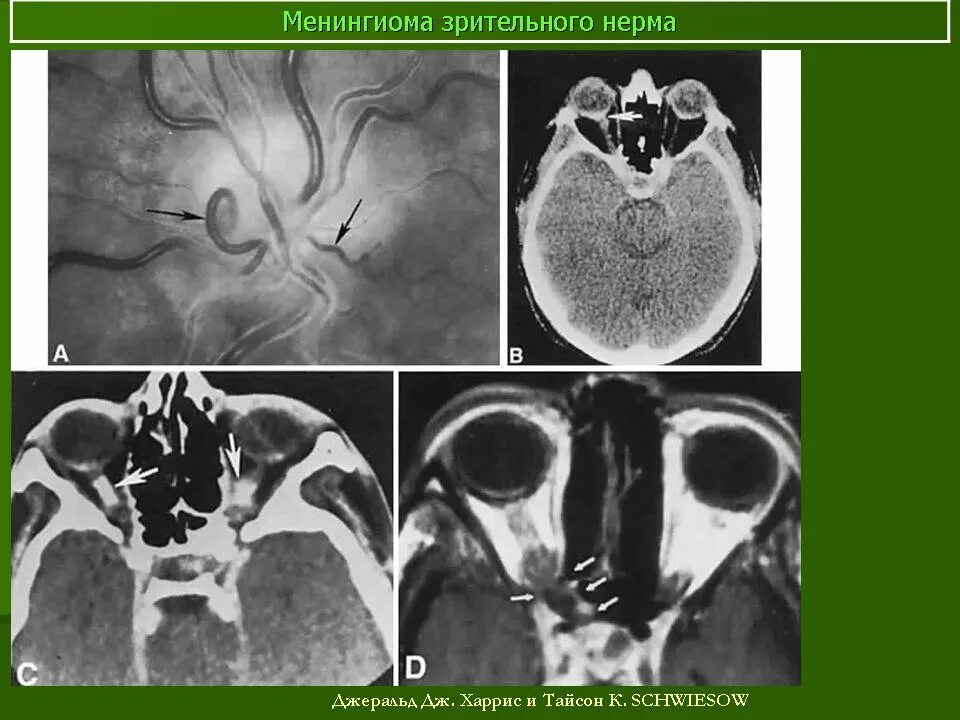

Менингиомы головного мозга мкб